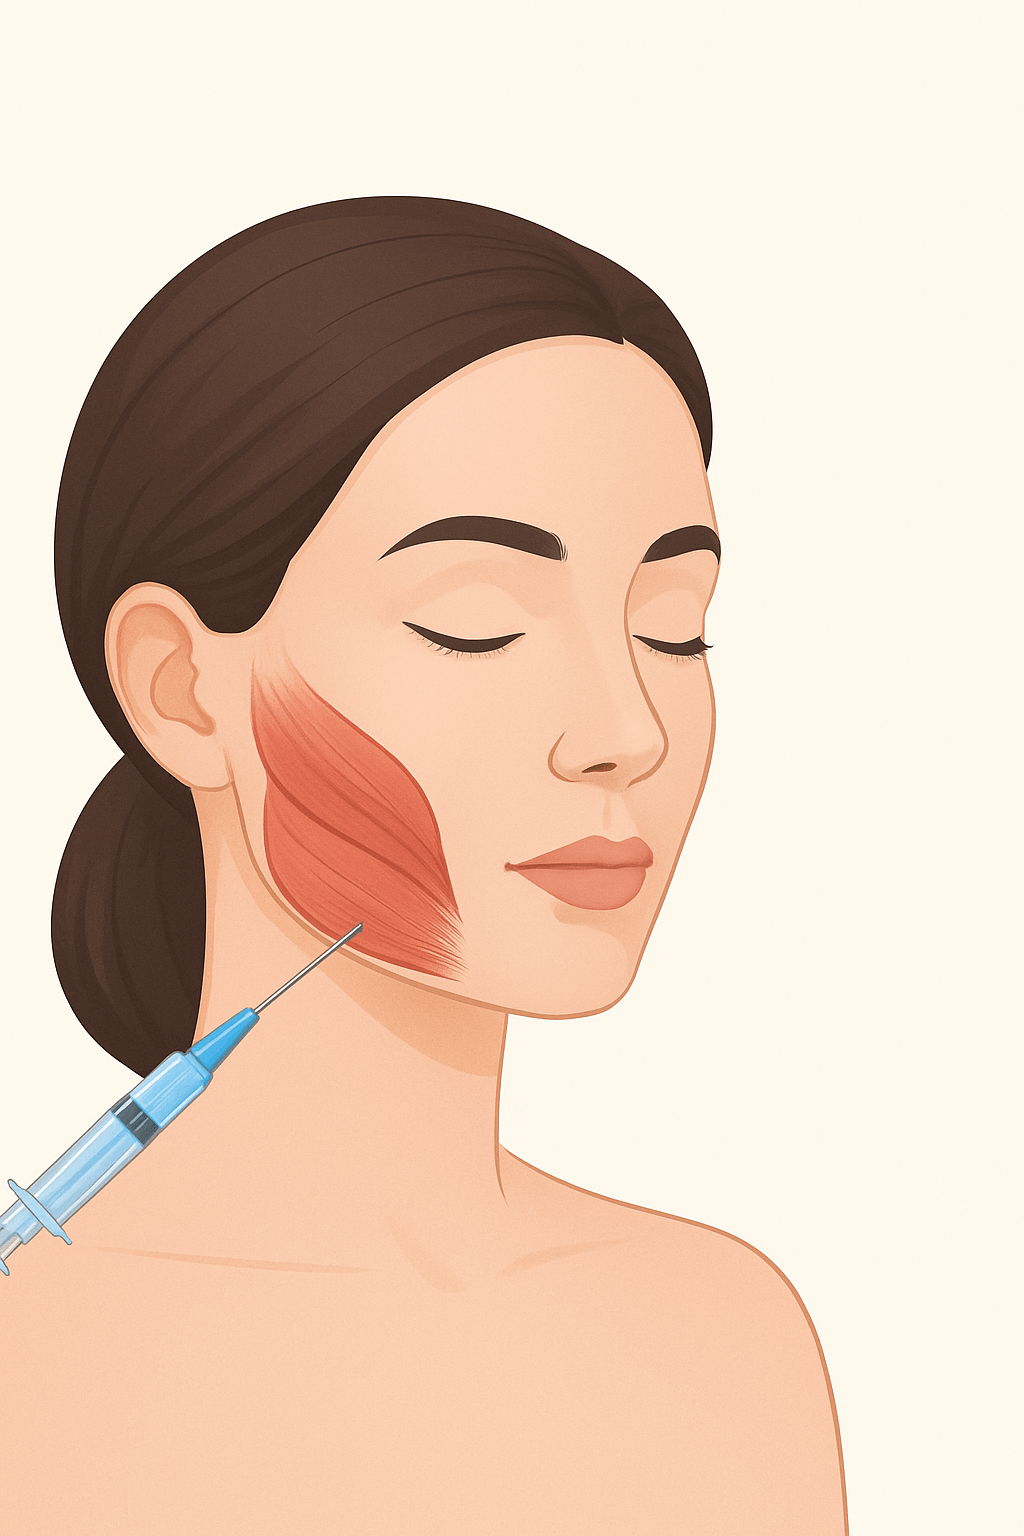

In recent years, one of the most popular treatments in both aesthetic and functional dentistry has been Masseter Botox. It is widely used for jawline slimming, creating a softer oval-shaped face, and treating teeth grinding (bruxism).

The masseter is one of the strongest muscles in the jaw, responsible for chewing. Overuse or hypertrophy of this muscle can cause:

What Is Masseter Botox?

Masseter Botox is the injection of botulinum toxin into the masseter muscle. It reduces the muscle’s overactivity, offering both aesthetic and therapeutic benefits.